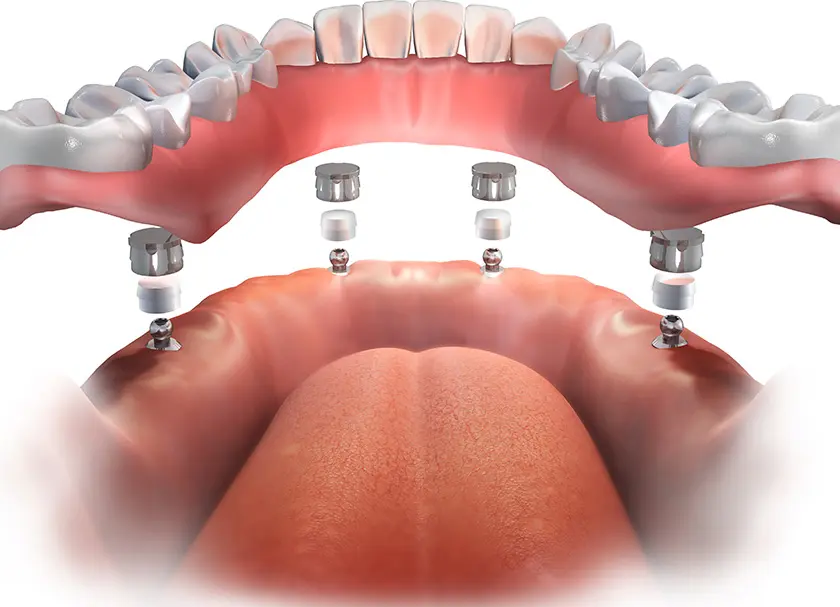

All on 4 dental implants is a unique technique of dental implant placement in Delhi in which 4 titanium screws that are medically approved are placed in the teeth area to support the entire teeth placement.

The dental tools are used to drill the holes and points are marked for drilling to ensure that the remaining part of the facial anatomy such as nerves and sinuses are not affected. The implants are then placed and tightened to the requirement and the surrounding gum tissues of the implants are closed with sutures. The abutments are next placed and fixed to the ends of the implants. The abutment acts as the holding anchor for the dental crowns.

Once the abutments are placed, the contact points where the abutments meet are drilled to ensure that the temporary crowns can be well-placed and the bite pattern is checked during this process so that any corrections of the jaw structure needed are done at this stage itself.